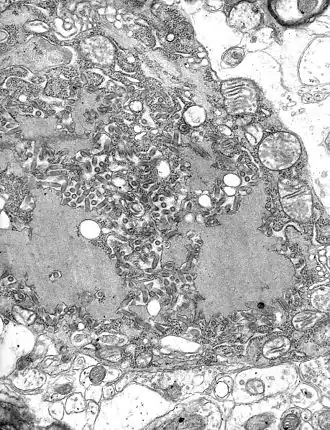

| Электронная микрофотография вируса бешенства, на фотографии также видны тельца Бабеша — Негри | |

Вирус размножается в нервных клетках организма, образуя тельца Бабеша — Негри. Экземпляры вируса переносятся через аксоны нейронов со скоростью приблизительно 3 мм/час. Достигая спинного и головного мозга, они вызывают менингоэнцефалит. В нервной системе вирус вызывает воспалительные, дистрофические и некротические изменения. Гибель животных и человека наступает вследствие асфиксии и остановки сердца[12].